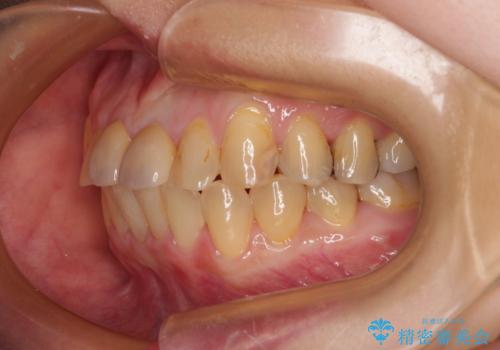

前歯のデコボコをワイヤー矯正できれいに整える

気になっていた前歯の変色も、矯正治療後にオールセラミッククラウンにて補綴治療を行うこととしました。

舌の突出癖により治療期間中に開咬となり、治療が長引きましたが、口元も治療前よりも引っ込めることができ、すっきりとした仕上がりとなりました。